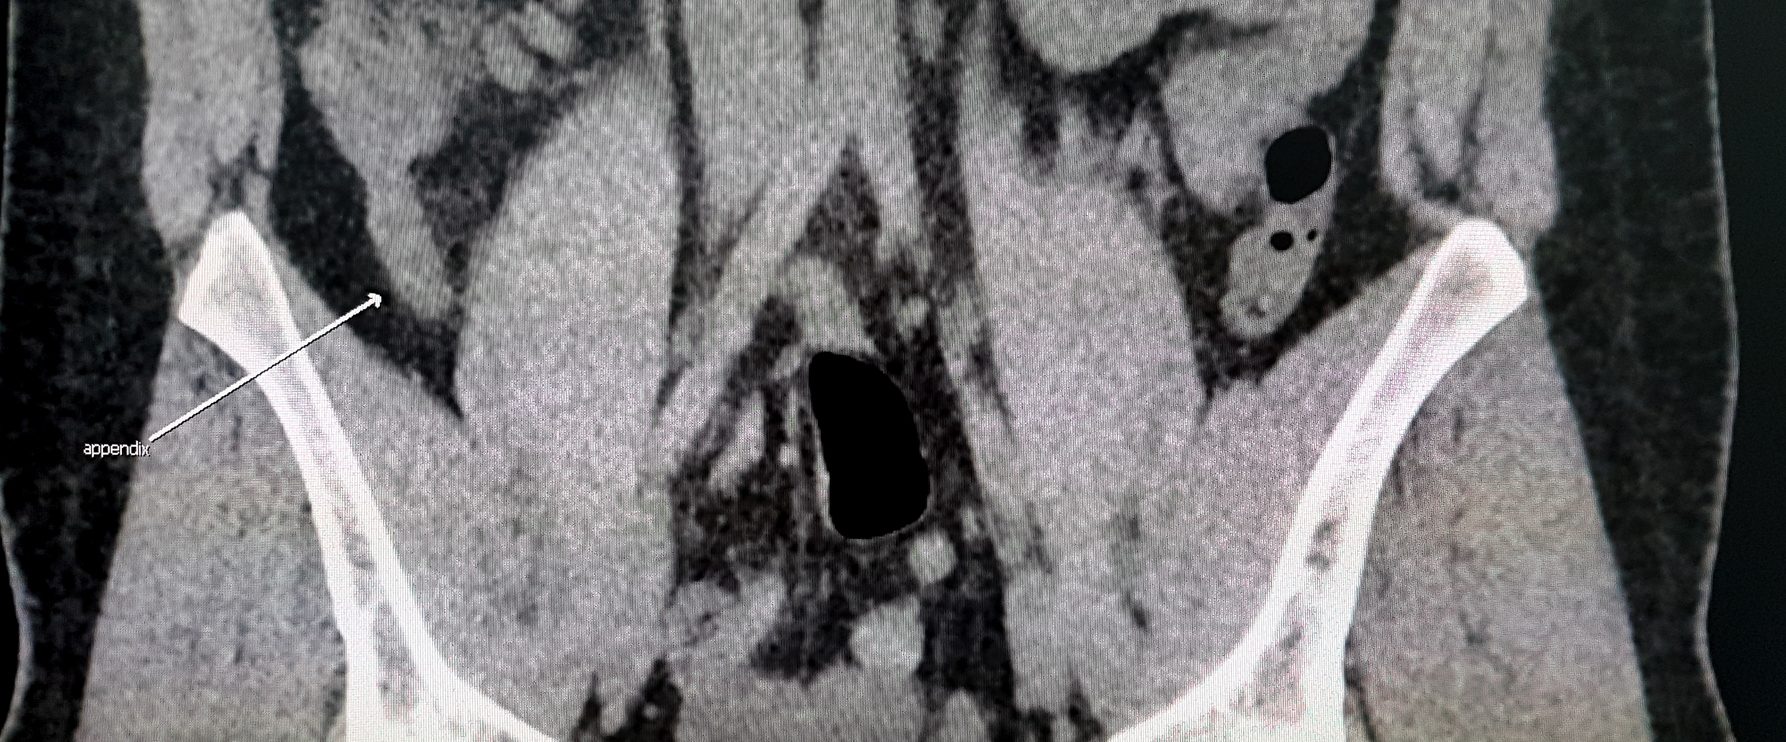

The surgical procedure to remove the appendixn is called an appendectomy. It is generally a emergency surgery, that’s performed to treat appendicitis – which is an inflammatory condition of the appendix.

Appendicitis is typically caused by a blockage of the hollow portion of the appendix.

Appendicitis. Source: msdmanuals

This blockage results in a build up of pressure and decreased blood flow to the appendix, and bacterial growth inside the appendix will cause an inflammatory response. Left untreated, an inflamed appendix will eventually burst spilling its infectious materials into the surrounding abdominal cavity – the consequences of which can be serious: in 2015, 50,000 people around the world died of appendicitis.